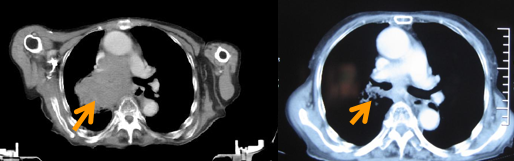

蔡叔是一位中晚期肺癌患者,在经过一段时间的绝望和挣扎后,来到我院寻求治疗的可能性。经过肿瘤科专家通过对他身体进行综合评估后,为他制定了放化疗联合治疗方案。

经过不懈的努力与坚持,蔡叔的病情得到了显著的改善,肺部病灶也逐渐消失,生活逐渐回归正轨。

治疗前 治疗后5月